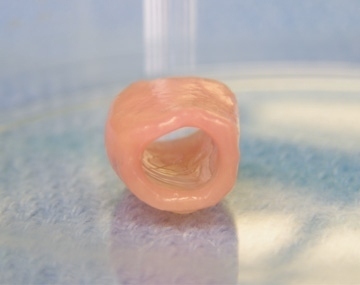

10. Injectable tissue engineering.